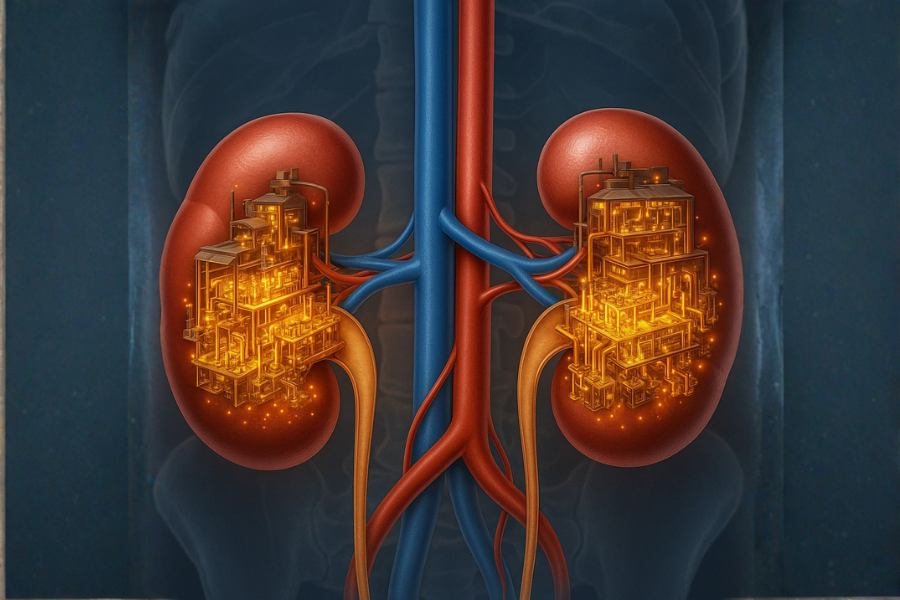

Thận được ví như nhà máy lọc thầm lặng của cơ thể. Mỗi ngày, thận lọc hàng trăm lít máu, loại bỏ chất thải, cân bằng nước – điện giải, điều hòa huyết áp và hỗ trợ tạo máu. Khi một phần nephron bị tổn thương, các nephron còn lại sẽ tăng công suất làm việc để bù trừ.

“Nhà máy lọc” thận hoạt động bù trừ nên suy thận giai đoạn sớm không có triệu chứng rõ ràng.